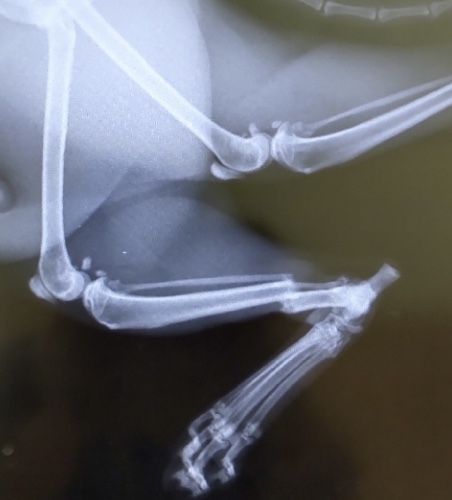

猫の骨折。治療費はどのくらいかかる? 2022 2/04 2022年2月4日 体調不良の柴犬コメちゃん 飼い犬が散歩に行きたがらない 関連記事 最近よく寝てばかりいる…冬の猫はどこまでが正常? 2026年1月24日 冬休み明けに増える?犬猫のストレスサインと生活リズムの整え方 2026年1月10日 シニア犬・猫の冬の過ごし方|寒さが苦手な子のケアポイント 2025年12月27日 なぜか残るペットのニオイ…大掃除で見直したい原因と対策 2025年12月20日 帰省や旅行で家を空ける時どうする?犬猫の留守番とペットシッター活用術 2025年12月13日 猫が水を飲まない時の冬の対策|寒い季節に増える理由と安全に水分補給させる方法 2025年12月6日 川崎市でペットと快適に暮らすには?ペットシッターが教える安心の環境づくり 2025年11月22日 犬が見せるしぐさでわかる!本当に伝えたい気持ちとサインの意味 2025年11月15日